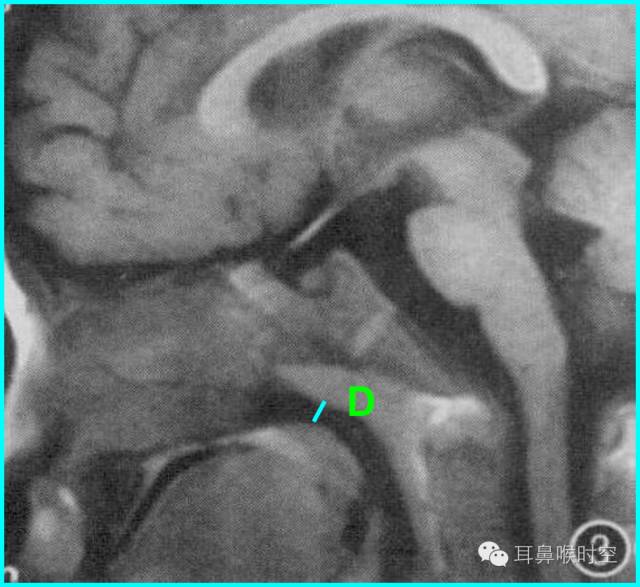

根据经典Fujioka 等 X 线平片测量法原理:

A/ N 比:测量腺样体最大厚度与自硬腭上缘到颅底蝶枕骨的软骨结合部的距离之比

PAS:后气道间隙(pharyngealairway space , PAS)的宽度(软腭表面与腺样体表面之间有效气道宽度)。

采用SE 序列矢状面T1WI

选择正中矢状面,分别测量两条径线(图1、2)

N 线:即从蝶骨体2枕骨斜坡的软骨结合部后缘(O点)至硬腭与软腭上缘交界处的连线N

A 线:过O点沿枕骨斜坡下缘作延长线L,取腺样体下缘最凸点作L线的垂直线。

A/N比:分别测A、N值,计算A/N 比

程万民等 测量:

60例4~14岁儿童,认为

A/N 比≥0.71

PAS≤3mm

为病理性肥大标准和手术指征。